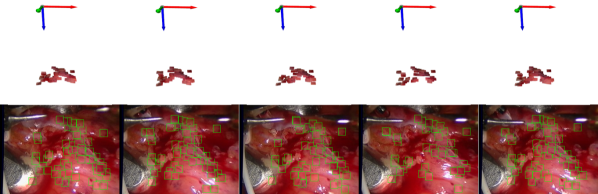

VI-B Deformable Tracking with Static Camera

1st-2nd rows, kinect T-Shirt dataset, frames # 0,# 70,# 150,# 250 and #300. 3rd-4th rows kinect Paper dataset, frames # 0,# 70,# 130,# 160 and #180. 5th-6th rows Hamlyn 4 (Heart sequence), frames # 0,# 12,# 16,# 26 and #40. 7th-8th Hamlyn 21 (Liver sequence), frames # 750,# 800,# 850,# 900 and #950.

In this section, we analyse the performance of deformable tracking with static camera in real sequences. The CVLab’s, T-shirt and paper dataset were recorded with a Kinect RGB-D camera. We also test intracorporeal sequences from the Hamlyn Dataset, in this case with stereo camera. We use the first depth image to initialise the surfels, i.e. the position, Jacobian and texture of each surfel. Notice that our system is monocular, hence we only process the gray images obtained with the RGB-D camera or with the left camera.

We have seen that assuming smooth surfaces improves the results in the paper area. However, this precludes the usage of this method in discontinuous surfaces. In contrast, as we have not assumed any regularizer between the individual surfels, we can track surfels not only on the paper area, but also on the person’s T-Shirt and on the white board (See Fig. 4). Discontinuities raise other challenges like occlusions that are successfully managed with the saturation of the photometric error.